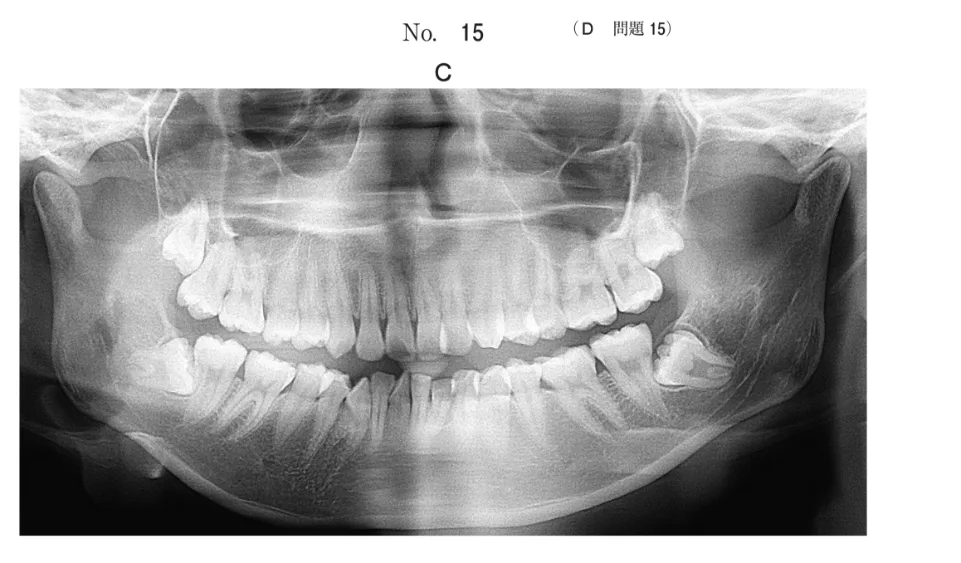

HOT ! 歯科矯正学 歯科矯正学 | 歯科国試ドットコム

歯科矯正学 歯科矯正学 | 歯科国試ドットコムの詳細情報

歯科矯正学 | 歯科国試ドットコム。コラボ矯正|大阪梅田の大阪H2B歯科・矯正歯科。シエン社 | 歯科矯正。歯科矯正学 | 歯科国試ドットコム。「歯科矯正学」葛西一貴 / 飯田順一郎定価: ¥ 14300#葛西一貴 #飯田順一郎 #本 #自然/医療・薬学・健康

• 歯科矯正学 | 歯科国試ドットコム

• コラボ矯正|大阪梅田の大阪H2B歯科・矯正歯科

• シエン社 | 歯科矯正